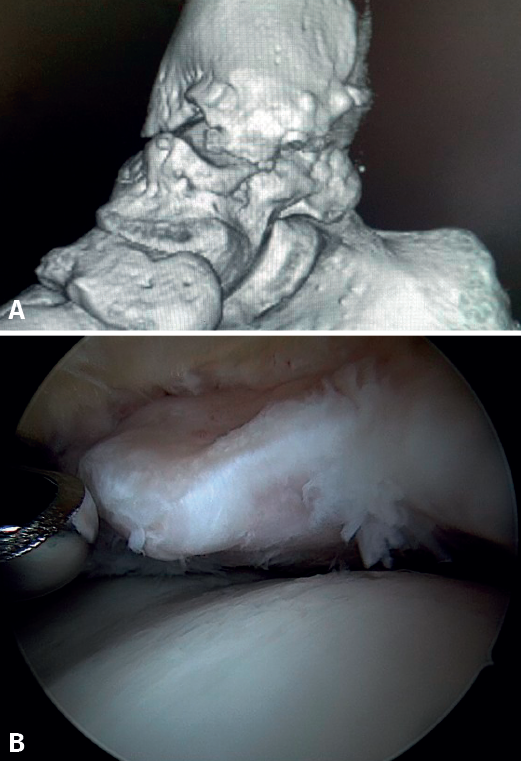

Bony AAI due to osteophytes has also been linked to the presence of chronic instability. It has been postulated that altered joint kinematics secondary to ligament insufficiency favors the development of osteophytes in the anterior region of the tibia and talus(36,37). Recent studies have questioned the theory of repeated capsular traction as the origin of osteophytes in sports(38), as it is easily demonstrated that osteophytes are located intra-articular within the capsular insertion, in the context of ankle arthroscopy (Figure 2). Therefore, ankle dorsiflexion arthroscopy is essential to safely resect osteophytes without damage to the capsule or overlying structures, whereas the classical traction technique (invasive or otherwise) would make resection extremely difficult, and is thus not recommended nowadays for routine use(3,39). Vega distinguished between two types of osteophytes(3), according to whether they are caused by repetitive trauma (peak-shaped) or instability (visor-shaped). The concept of micro-instability is associated with repetitive micro-trauma, which could be the origin of osteophytes with this characteristic morphology (Figure 3).

Figure 1. Bony impingement between the talus and tibia. A: ankle in plantar flexion; B: ankle in dorsiflexion showing impingement between the two osteophytes.

Figure 2. Anterior tibial osteophyte. A: in dorsiflexion the capsule separates from the osteophyte allowing its resection (B) through reaming.

Figure 3. Osteophyte due to chronic instability. A: the osteophyte forms a bone block extending over the anterior margin of the tibial plafond and the anterior aspect of the medial malleolus; B: arthroscopic view.